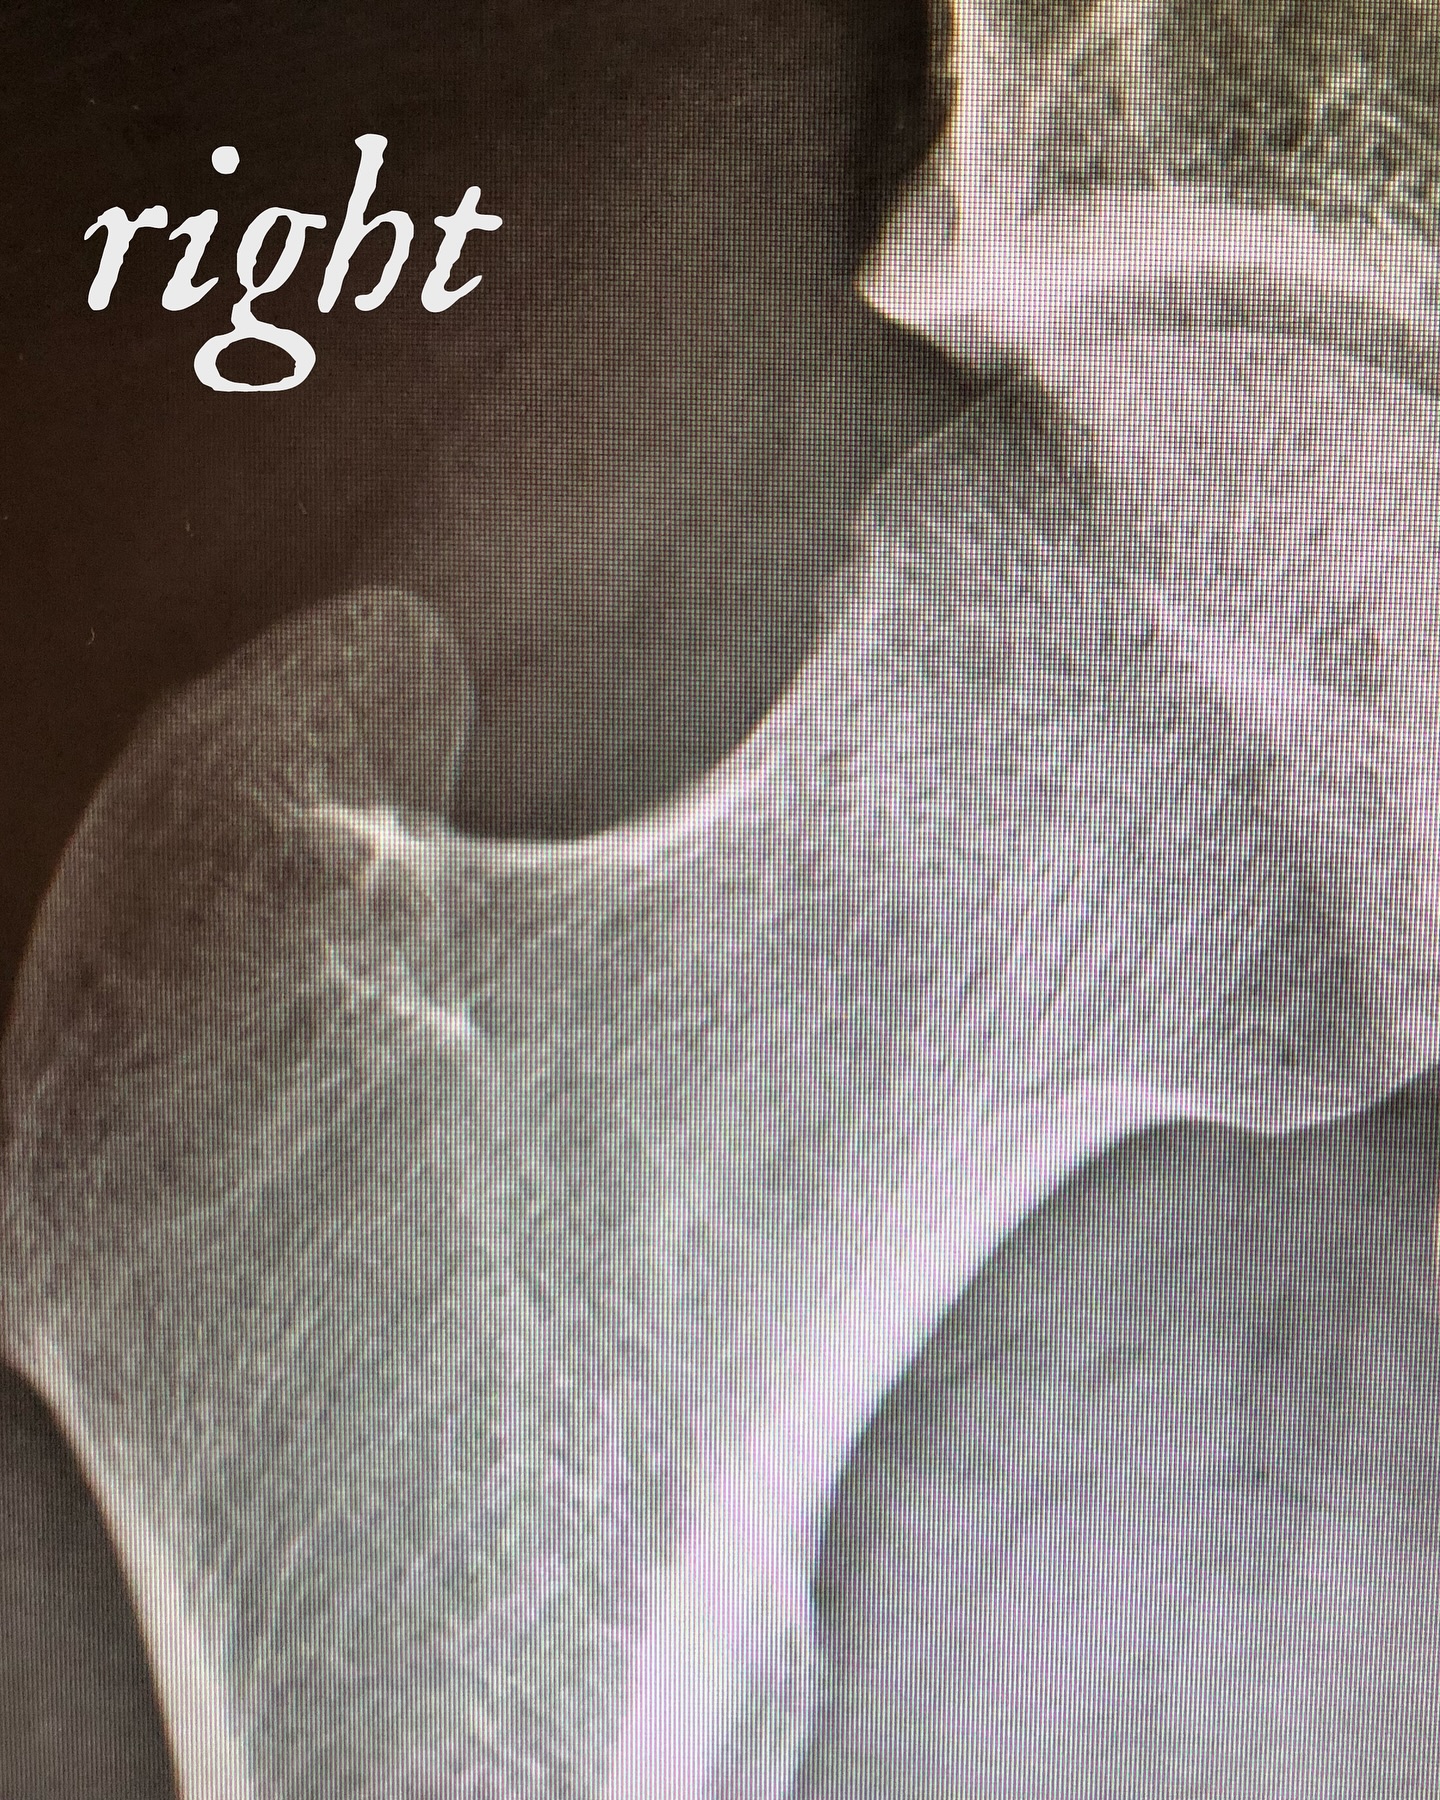

He continued, “Frustrated and in search of a solution, an MRI in October of 2020 indicated that I had suffered a ‘femoroacetabular impingement’ as the result of an abnormal bone growth on the neck of my left femur bashing up against my hip labrum when I’d go running. My doctor — who I’d known had helped many professional athletes with the same condition — recommended an arthroscopic procedure to correct the issue.”

In November 2023, Jay revealed his health struggles after announcing he left Slipknot for ‘creative’ reasons. He posted photos on Instagram showing himself with crutches and in the hospital, explaining his ongoing health plan.